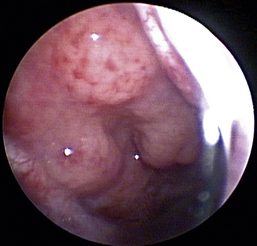

The hallmark symptom of nasopharyngeal disease is stertor. Discharge, sneezing, reverse sneezing, and hacking may be present variably. If the main complaint is noisy breathing and not productive sneezing with nasal discharge, the nasopharynx may be the site of primary disease. The most common primary problems in the nasopharynx in cats are inflammatory polyps and tumors.12,13 Cats with polyps are generally young and have a history of noisy breathing. Sneezing and mucopurulent nasal discharge may be present, but the chief complaint is stertor and increased respiratory effort. This is a problem that often requires otoscopic as well as rhinoscopic intervention. With the patient placed in dorsal recumbency, the soft palate is reflected rostrally with the use of a spay hook, and the polyp is removed via traction and avulsion (Figures 19-18 and 19-19). The eustachian tube orifices can generally be directly visualized and any remaining tissue removed, if present. Both ears should be carefully examined, and transtympanic bulla curettage should be performed to remove any middle ear proliferative tissue (see Chapter 20). In older cats with similar symptoms, a neoplasm in the nasopharynx is more likely, and rhinoscopy is often much more rewarding (Figure 19-20). Foreign bodies can become lodged in this area after vomiting or pharyngeal nasopharyngeal spasms induced by attempted swallowing of the foreign object. Nasal and nasopharyngeal stenosis after trauma, nasogastric reflux,14 and chronic rhinitis can occur in dogs and cats (Figures 19-21 through 19-23). Reflux can occur during general anesthesia and can be a helpful clue if postoperative symptoms arise and persist. Congenital choanal atresia and nasopharyngeal dysgenesis have also been reported in dogs.15,16 Nonspecific chronic inflammation of the nasopharynx causes a cobblestone appearance of the mucosa due to the formation of hyperplastic lymphoid follicles (Figures 19-24 and 19-25). Chronic inflammation may be the result of a lymphoplasmacytic rhinitis complex or sometimes may be secondary to otitis media and middle ear drainage of infected secretions via the eustachian tube. Otoscopy is recommended in any patient with nasopharyngitis of unknown origin. CT studies performed in a population of 45 cats with chronic sinonasal discharge revealed effusive bulla disease in 28% of symptomatic cats.17 Unfortunately, we are unable to differentiate primary and secondary pathology based on the concurrence of nasal and middle ear disease. Regardless of the knowledge of the primary cause, both inflammatory foci should be treated to achieve symptom relief.

image

Figure 19-18 Feline nasopharyngeal polyp visualization via soft palate retraction.